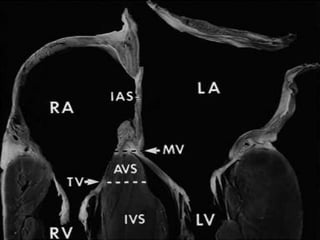

• In AVSDs, the atrioventricular valves have the

same septal insertion level in contrast to the

leaflet arrangement in the normal heart.

• The distance from the cardiac crux to the left

ventricular apex is foreshortened, and the

distance from the apex to the aortic valve is

increased in contrast to normal heart.

• In the normal heart, the aortic valve is wedged

between the mitral and tricuspid annuli.

• In AVSD the aortic valve is displaced or sprung

anteriorly .